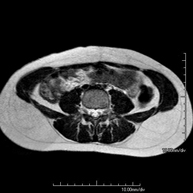

- Prostate MRI (endorectal prostate MRI + spectroscopy)

This non-invasive diagnostic procedure uses an electromagnetic field and radio waves (from a transmitter and receiver) to acquire high-definition anatomical images of the prostate gland. It is a radiation-free procedure. An endorectal coil is used to obtain images of the prostate with maximum anatomical definition, enabling a spectroscopic screening (molecular-level study to define malignant and tumour cells). A paramagnetic contrast study is also performed to provide better tissue definition. This screening takes about 40 minutes, during which time the patient should remain as still as possible. Prior preparation requires colon cleansing. This test is especially recommended for patients with suspected prostate cancer, known prostate cancer for tumour staging, prostate tumour localisation as a guide or map for biopsy, follow-up of patients with prostate cancer treated with surgery or radiotherapy, suspected recurrence of prostate cancer, etc.